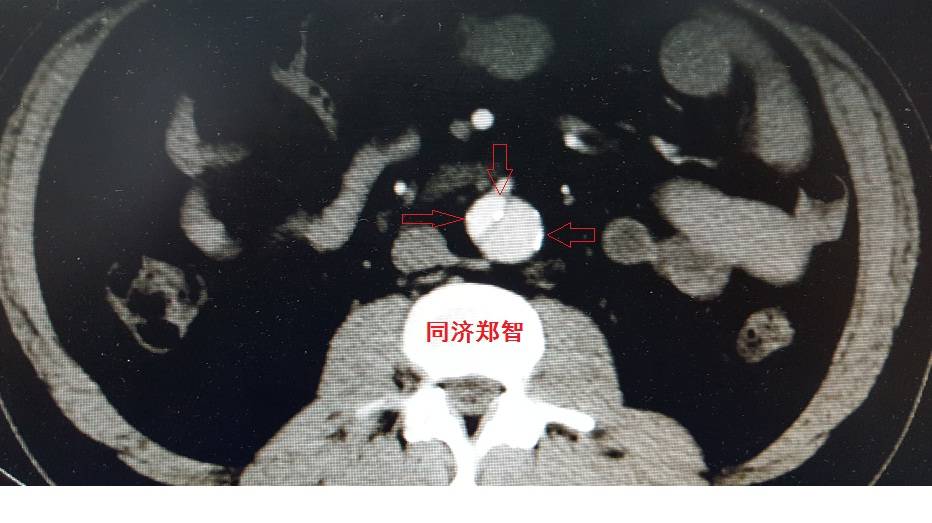

病例十

腹主动脉平扫CT提示正常外周一圈的钙化影中有内移的钙化影(红色箭头所示),CTA 证实为腹主动脉夹层